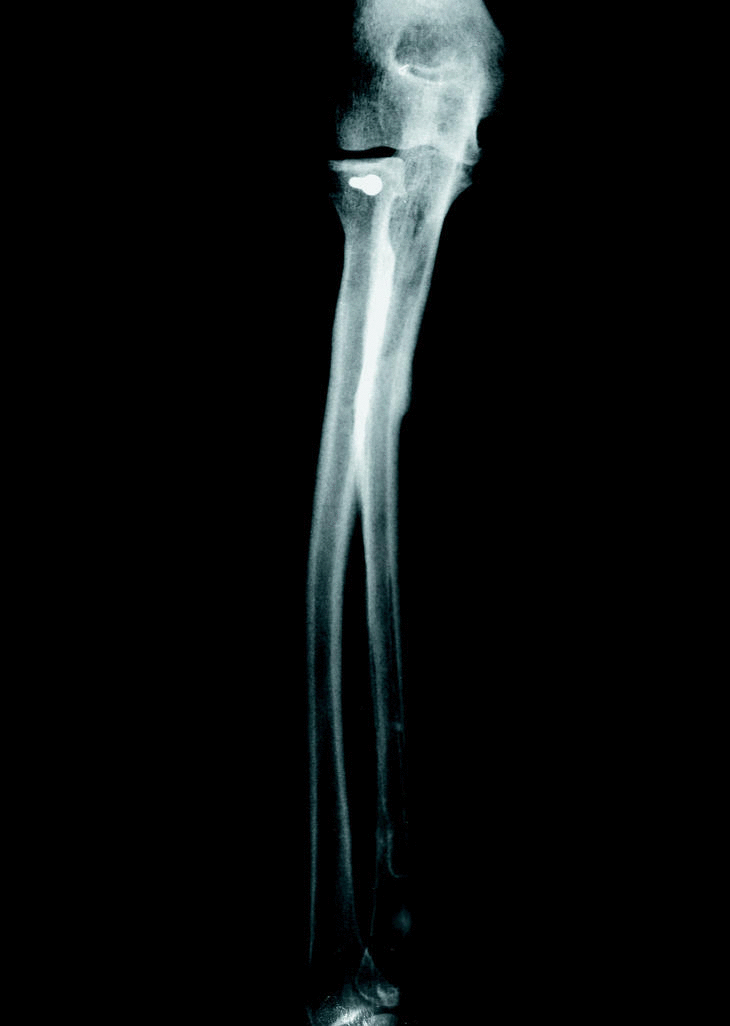

En todos los casos, excepto en uno, se empleó un montaje con bloqueo estático del clavo aplicando compresión al foco de fractura. En los casos en que existió una fractura simultánea del radio, se sintetizó esta última con una placa a compresión de 8 tornillos. En un caso con fractura conminuta de la cabeza del radio (Fig. 2), se llevó a cabo una osteosíntesis directa de la misma con tornillo de minifragmentos (Fig. 3).

Figura 2. Rx postoperatoria donde se aprecia una fractura parcelaria de la cabeza del radio.

Figura 3. Rx postoperatoria al mes una vez llevada a cabo la osteosíntesis de la cabeza radial.

El caso más complejo fue el de una mujer de 42 años, laboralmente activa, que presentó tras una caída casual una luxación de codo asociada a una fractura-luxación de Monteggia. Inicialmente se redujo la luxación y se sintetizó el cúbito; tras el control radiológico se apreció una fractura parcelaria de la cabeza del radio que precisó una osteosíntesis directa con tornillo. Después de lograr la consolidación, a los 3 meses, con una completa recuperación funcional del antebrazo se decidió retirar el clavo con anestesia regional (Figs. 1-6).